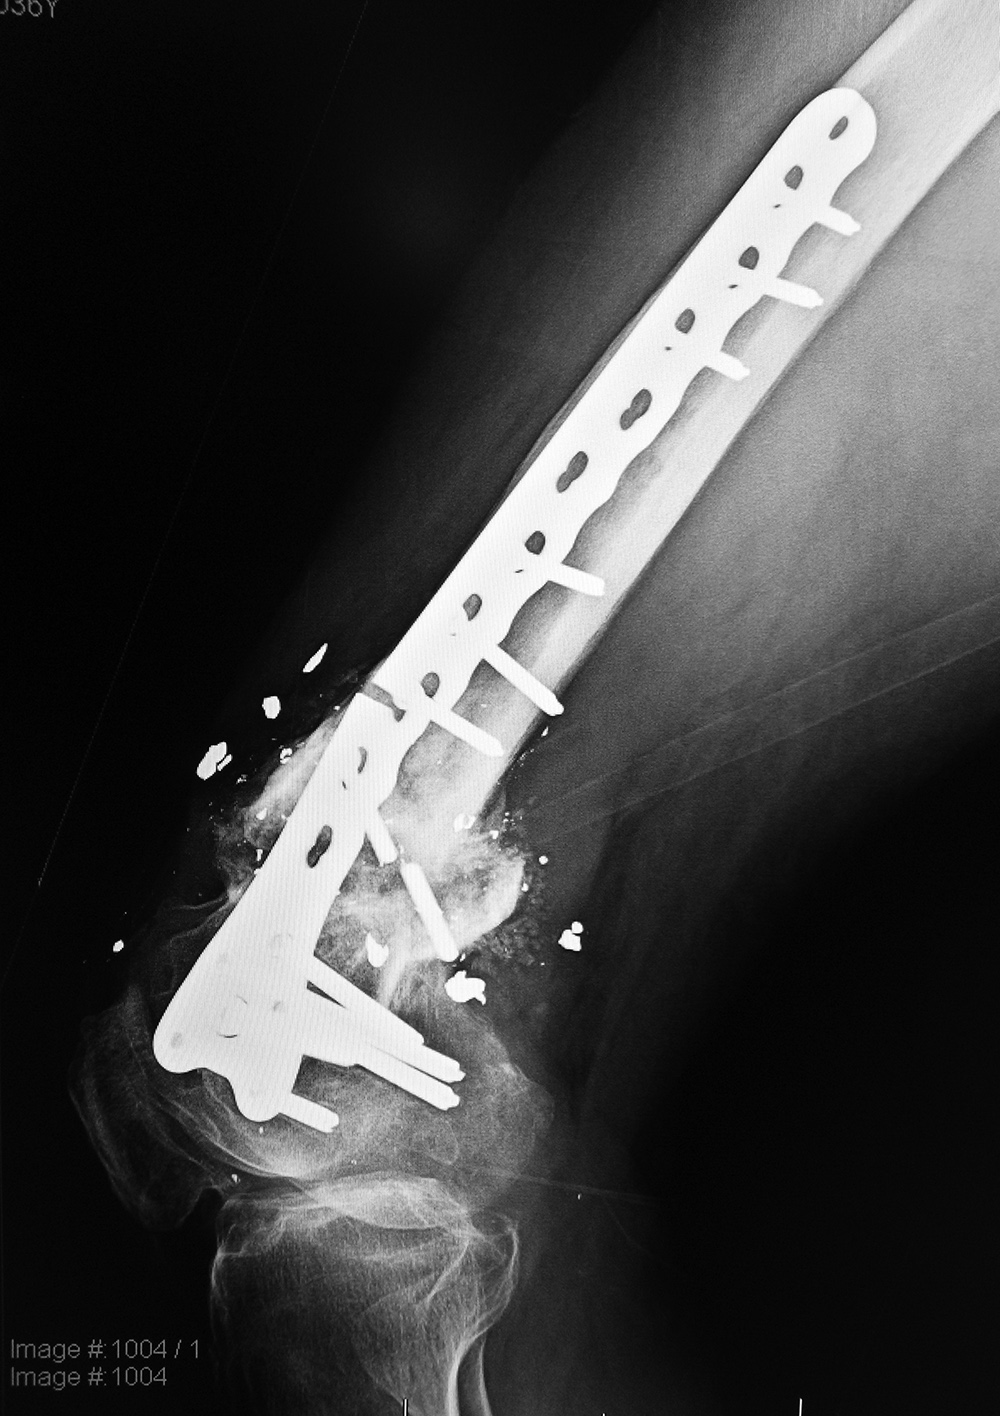

| Right femur periarticular plate breakage and chronic fracture nonunion |

| 36 year-old man with bullet wound in 2003 complicated by femur fracture infected non-union treated by multiple attempts with external fixation and open reduction and internal fixation (ORIF). Radiography 12 years later shows chronic fracture hypertrophic nonunion, multiple shrapnel fragments, and breakage of a periarticular fixation plate. |